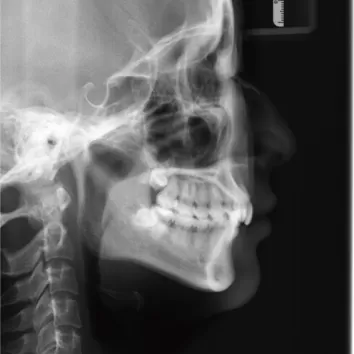

X-rays before treatment

[Panoramic Radiography/Lateral Cephalogram]